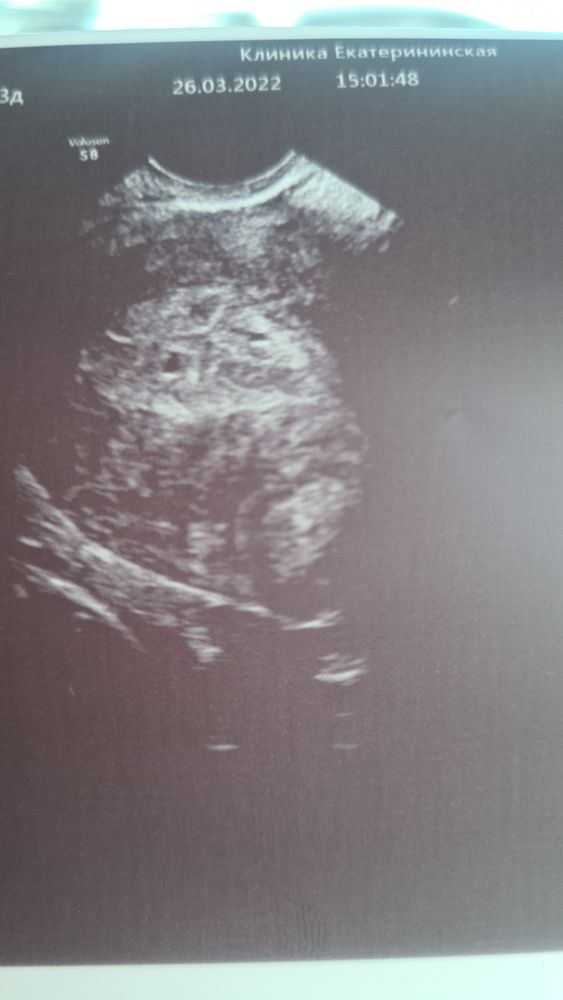

Узи 4 нед.4 дня , двойня?

Всем добрый вечер. Может есть здесь узисты😅 Понятно, что я верю врачу у которого была,нооооо видимо не верю своим ушам и вообще всему происходящему. Она увидела двойню, контрольное узи через 2 недели. Говорит, может быть одно ложное, пока трудно разобрать. Кто-нибудь ещё видит два?)))я не соображу где смотреть, она мне показывала, но после слов- у вас есть в роду двойни,все как в тумане.

У подруги тоже было подозрение на двойню. Потом в итоге один остался, а другой исчез. У Вас два кружочка)